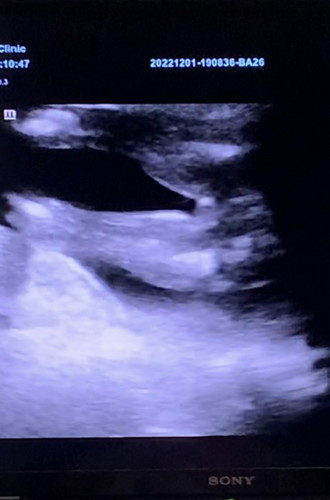

17week แบบนี้ผู้หญิงชัวร์มั๊ยคะ มีใครได้ลูกสาวซาวเจอแบบนี้เลยมั๊ยคะ

ผู้หญิงค่ะ 😊